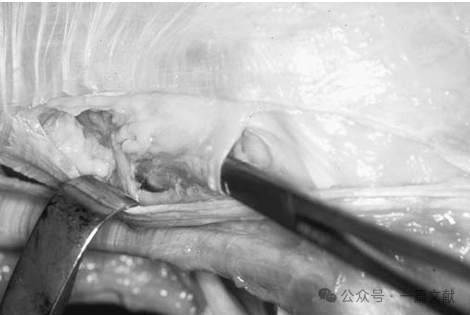

2.膝关节腘肌复合体:除腓侧副韧带外,腘肌复合体构成膝关节后外侧另一重要的静态稳定结构。该复合体彼此形成复杂的相互作用:包括腘肌腱股骨附着部、三组腘肌半月板束(前下束、后上束与后下束)、分前后两束的腘腓韧带、后关节囊及外侧半月板后角的腱膜附着部,以及腘肌肌腹本身。腘肌腱股骨附着部始终位于腓侧副韧带股骨附着点的前方。

关节镜下腘肌腱走行:当腘肌腱穿行至腘肌裂孔时,通过前下、后上及后下三组腘肌半月板束附着于外侧半月板。这些半月板束形成"轮箍样"结构,将腘肌腱与腘肌裂孔处的外侧半月板紧密连接。